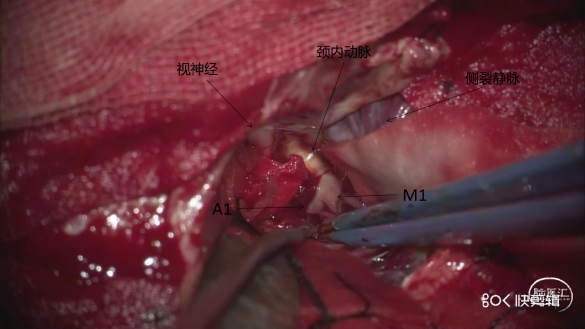

术中照片

全麻成功后,取平卧位,头左偏约40°,标记发髻内右侧翼点入路切口,于关建孔、顶部钻孔2枚,去除骨瓣,咬平蝶骨嵴,硬膜张力不高,弧形打开硬膜,由外向内分离外侧裂,显露视神经及ICA近端,抬额叶过程中动脉瘤顶部视神经旁一小穿支血管破裂出血,给予明胶海绵、棉片压迫,临时阻断C6近端,见瘤体呈红色、壁薄,夹闭瘤颈过程中,瘤顶部破裂出血,瘤颈1次夹闭成功。再依次分离M1主干、上干及下干,暴露分叉动脉瘤,临时阻断M1,夹闭动脉瘤,调整瘤夹位置直至夹闭完全。